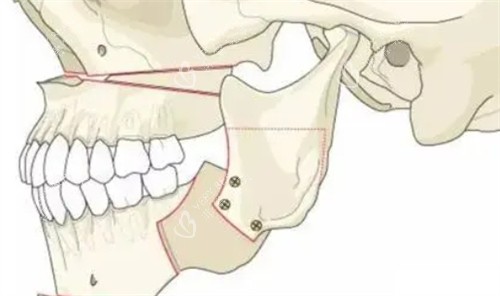

面诊那天,医生拿着我的CT片,指着骨头说:“你这是上颌前突+下颌后缩,得做双颌手术——上颌截骨后移,下颌截骨前移。”我听得云里雾里,只问了一句:“能让我侧脸不凸吗?”医生笑:“术后你的侧脸会立体很多,但得做好心理准备:前三个月肿得像猪头,半年才能正常吃饭。”我咬咬牙:“做!”

术后前三个月,我像“养伤正规户”——每天喝粥、吃蒸蛋,连苹果都得打成泥。第四个月开始,能嚼软饭了,但硬的东西还是不敢碰。第六个月复查时,医生拿着我的对比照说:“侧脸变化非常大,上颌收了5毫米,下颌前移了3毫米,现在比例很协调。”